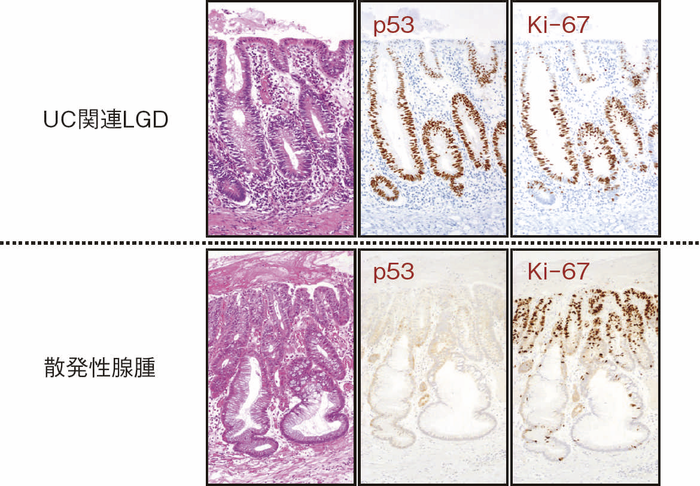

- 組織学的特徴

dysplasiaはその異型度によりLGDとHGDに二分される(図9)。LGDは基本的に核の極性が比較的保たれており,表層への分化傾向がみられることを特徴とし,しばしば反応性異型との鑑別を要する。多彩な形態像を示すこともdysplasiaの特徴である。味岡らは,UC関連大腸腫瘍を5つの特殊なパターン(表層分化を示す分化型腺癌,分化細胞を豊富にもつ分化型腺癌,分化細胞に乏しい分化型腺癌,未分化型腺癌または分化型腺癌の脱分化,癌の判定が困難な分化型腫瘍)に分類し報告している3)。2019年に出版されたWHO分類には,IBDを背景に発生する粘膜内腫瘍をInflammatory bowel disease-associated dysplasia of the colorectumと呼称し,組織形態に基づき,intestinal(adenomatous)subtype,serrated subtype,mucinous type,a subtype with eosinophilic cytoplasm and marked goblet cell depletion,crypt cell subtypeやこれらの組織像が混在したmixed subtypeなどが存在すると記載されている4)(図10)。

このように多彩な像を呈するdysplasiaでは,特に異型度が低い場合に反応性異型との鑑別にしばしば難渋するが,dystrophic goblet cell,endocrine cell hyperplasia,Paneth細胞化生などの特徴的な上皮細胞分化異常を示す特殊な異型上皮の存在が形態学的な鑑別として有用である。また,dysplasiaでは,腫瘍発生早期の段階よりTP53遺伝子異常が起こることが知られている。したがって,上記の形態学的な異常とともに,免疫染色におけるp53蛋白異常発現の有無が反応性異型や散発性腺腫との鑑別において重要となる(TP53遺伝子変異が見られる際には,免疫染色においてp53蛋白過剰発現あるいは完全欠失を示すことが知られている)。これまでに,一般大腸腺腫・癌ではp53蛋白過剰発現はその異型度に相関するのに対し(腺腫で0.8~3.4%,低異型度癌で35.3%,高異型度癌で71.7%),dysplasiaでは低異型度の段階から高頻度(75%)にp53蛋白過剰発現を呈することが報告されている5)。したがって,特に低異型度腫瘍でp53蛋白異常発現パターンを示す場合はdysplasiaの可能性が高く,反応性異型との鑑別において診断的意義が高い。また,表層分化傾向を示すLGDではp53蛋白の過剰発現がある場合でも表層部ではp53蛋白の発現減弱がしばしば観察されるのに対し(unique basal patternと呼ばれる),HGDでは全層性にp53蛋白過剰発現を示すことが多い。Ki-67(増殖マーカー)染色では,dysplasiaでは細胞増殖帯が粘膜深層~中層に位置するが(bottom-up pattern),散発性腺腫では細胞増殖帯が腺管表層~中層に分布することが知られている(top-down pattern)。これらの免疫染色パターンは,dysplasiaと反応性異型や散発性腺腫との鑑別の際に重要な手がかりとなる(図9,図11)(CQ 12,CQ 13)。

図11 LGDと散発性腺腫の代表的な病理組織像と特徴的免疫染色像

表層への分化傾向を示すLGDでは異型腺管深部側優位にp53蛋白過剰発現が見られるのに対し,散発性腺腫ではp53蛋白異常発現は認められない。また,Ki-67(増殖マーカー)染色においては,LGDでは細胞増殖帯が粘膜深層~中層に位置するが(bottom-up pattern),散発性腺腫では細胞増殖帯が腺管表層~中層に分布する(top-down pattern)(CQ 12,CQ 13)。